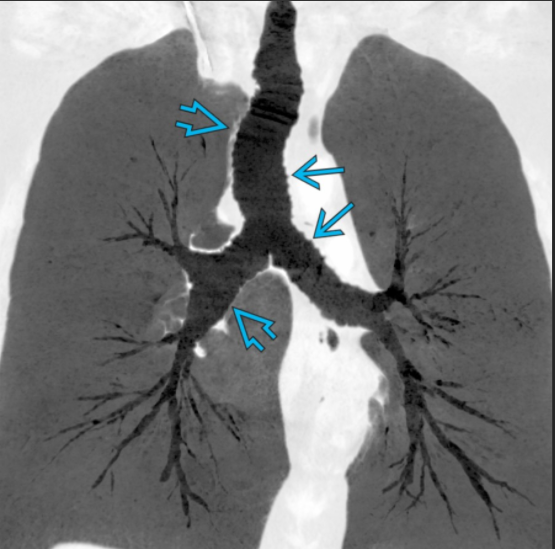

Tracheobronchomegaly (Mounier-Kuhn syndrome)

Dilatation of trachea & central bronchi that impairs ability to clear mucus

Atrophy or absence of elastic fibers & thinning of smooth muscle layer in trachea & main bronchi

Tracheobronchomegaly; Mounier-Kuhn syndrome

Coronal CECT of a patient with tracheobronchomegaly shows marked dilatation of the trachea (open arrow) and mainstem bronchi . The large airways have a corrugated appearance. Right lower lobe pneumonia (straight arrow) and paraseptal emphysema are also present.